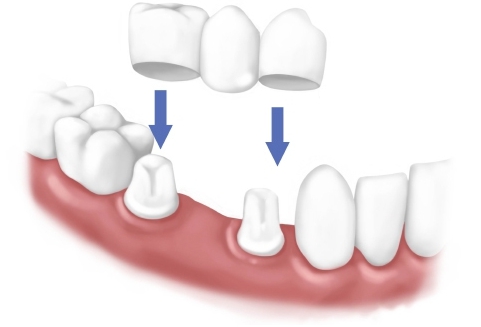

牙橋是什麼

牙橋的意思,就如同字面上的意思,就像一座橋。單獨少了一顆牙的時候,因為連牙根都沒了,沒辦法做全瓷冠套上,牙橋就需要透過修磨兩邊的牙齒,將他們連在一起,做成一組假牙。兩邊牙齒的作用就像是橋墩一樣,他們的任務就是支撐整組假牙的重量,兩顆牙要去支撐三顆牙齒咬合的力量,是非常辛苦的。因此牙橋的製作難度與受力更是需要考驗。那麼牙橋的好處呢?牙橋的好處有:速度快、不需要手術、所需的身體條件較低。缺點則是:需要修磨兩旁健康的牙齒,依照牙齒情況可能還需要做根管治療,三顆以上連在一起的假牙清潔起來可是非常麻煩的,若將來不幸壞掉的,可是要整組一起重新製作的。

缺牙的補救方法有牙橋和植牙兩種。牙橋是透過修磨缺牙兩邊的牙齒,將他們連在一起,做成一組假牙,好處是不需要手術,但可能耐受力不足,且清潔麻煩,若不幸壞掉要整組重做或再拔牙。相比之下植牙不需要修磨缺牙兩邊的牙齒,清潔方式較簡單,而且可以避免缺牙部分的顎骨內縮,影響外觀,不過植牙費用較牙橋貴、需要手術,手術前評估身體和口腔狀況的條件要求比較高。缺牙的治療方式要經過專業醫師評估,所以建議您填寫線上諮詢表單或致電欣鴻植牙會館,由我們為您安排免費諮詢,整體了解您的狀況後,依照您的身體情況、口腔狀況以及需求,為您做最適當的治療。